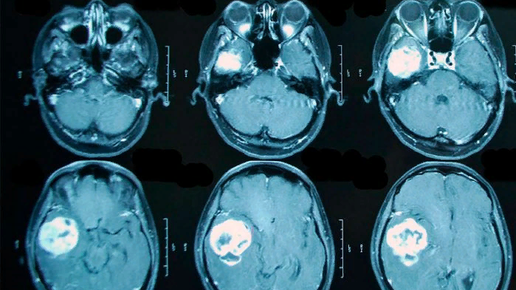

Сколько живут с опухолью головного мозга?

Одной из самых опасных и редких на сегодняшний день форм карциномы (злокачественного новообразования) является опухоль головного мозга. Сколько с ней живут? Что это за заболевание? Какие стадии бывают? Какие симптомы? Каковы прогнозы? Эти и другие вопросы необходимо рассмотреть, говоря о данной патологии. Причины заболевания Опухоль головного мозга — тяжело излечимое заболевание, способное привести к смерти пациента. Возникать оно может по различным причинам. Если в жизни человека присутствуют некоторые из них, то его можно отнести к группе риска...